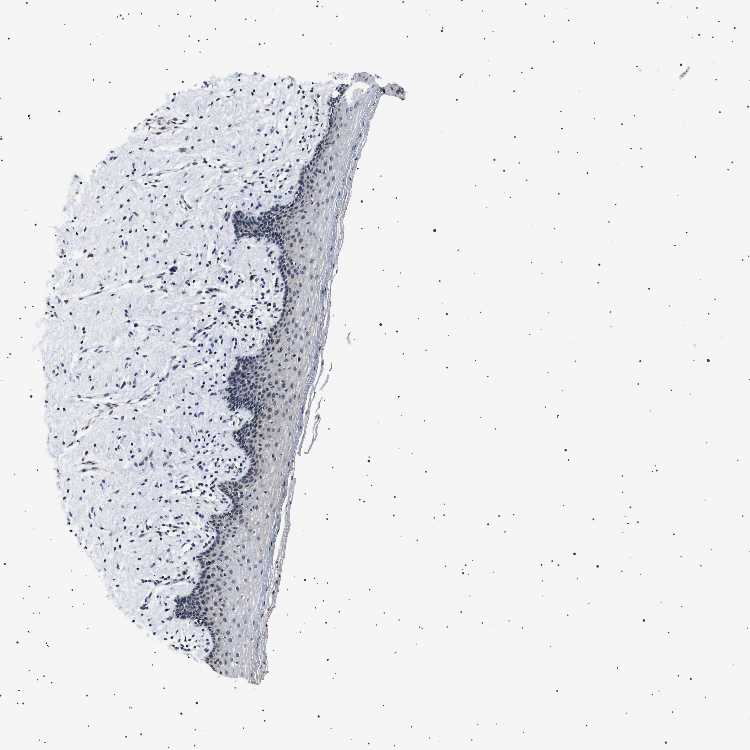

VAGINA - Antibody stainingi

Antibody staining in the annotated cell types in the current human tissue is reported as not detected, low, medium, or high, based on conventional immunohistochemistry profiling in selected tissues. This score is based on the combination of the staining intensity and fraction of stained cells.

Each image is clickable and will lead to virtual microscopy that enables deeper exploration of all samples and also displays staining intensity scores, fraction scores and subcellular localization as well as patient and tissue information for each sample.

Antibody HPA039867Antibody CAB020833

Squamous epithelial cells Not detectedNot detected